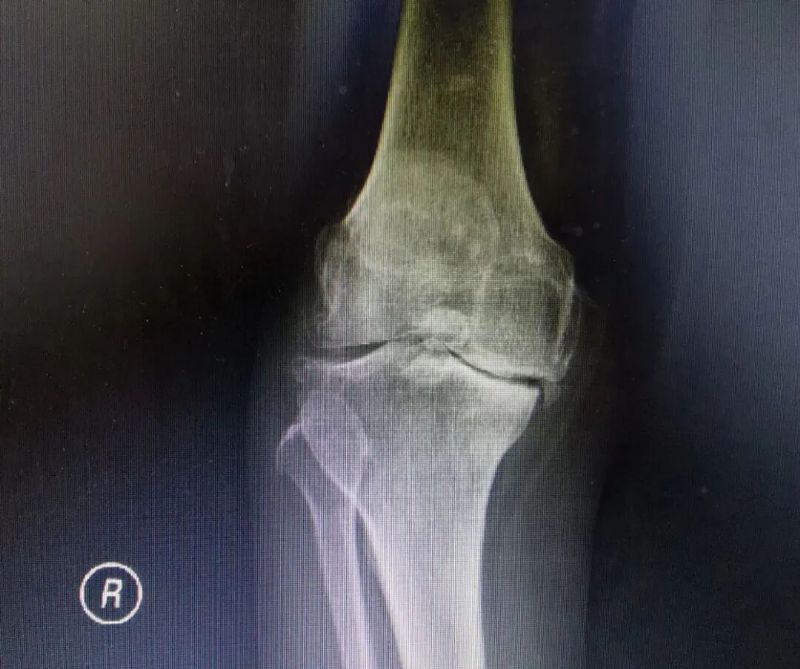

影像學檢查是診斷的重要手段。X線檢查就像給關節拍了一張“照片”,能夠清晰地顯示關節間隙變窄、骨質增生、軟骨下骨硬化等典型表現。而MRI檢查則更像是一部“高清攝像機”,能更清晰地觀察關節軟骨、半月板、滑膜等軟組織的病變情況,為醫生提供更準確的診斷依據。